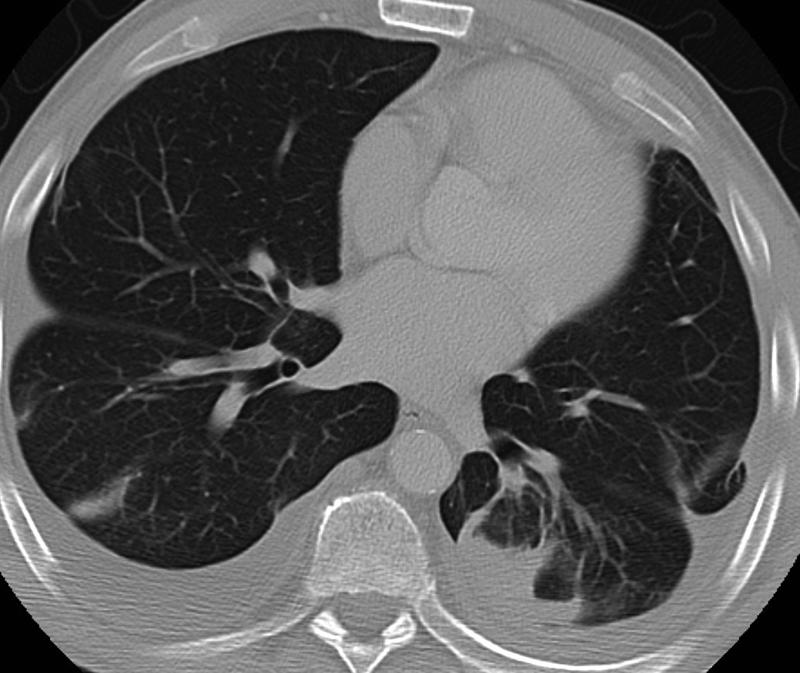

Rounded atelectasis case 2